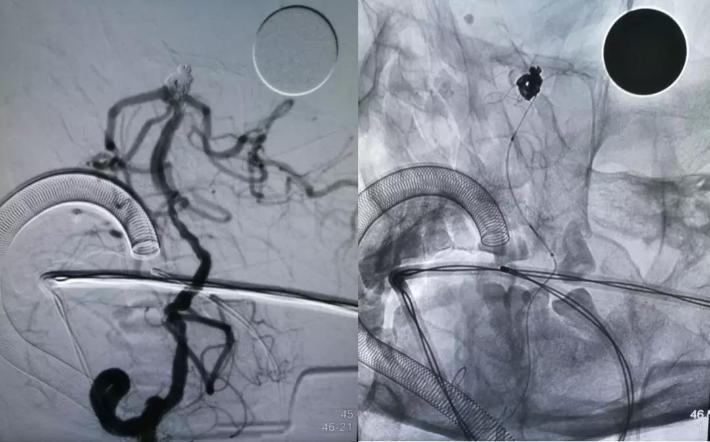

治疗后

对侧造影评估,前交通开放,左侧大脑前动脉经开放良好的前交通动脉向右侧大脑前动脉A2段各分支血管供血良好,结束手术